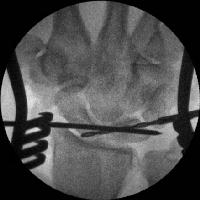

Scapholunate pins and bone anchors - intraoperative fluoroscopy.